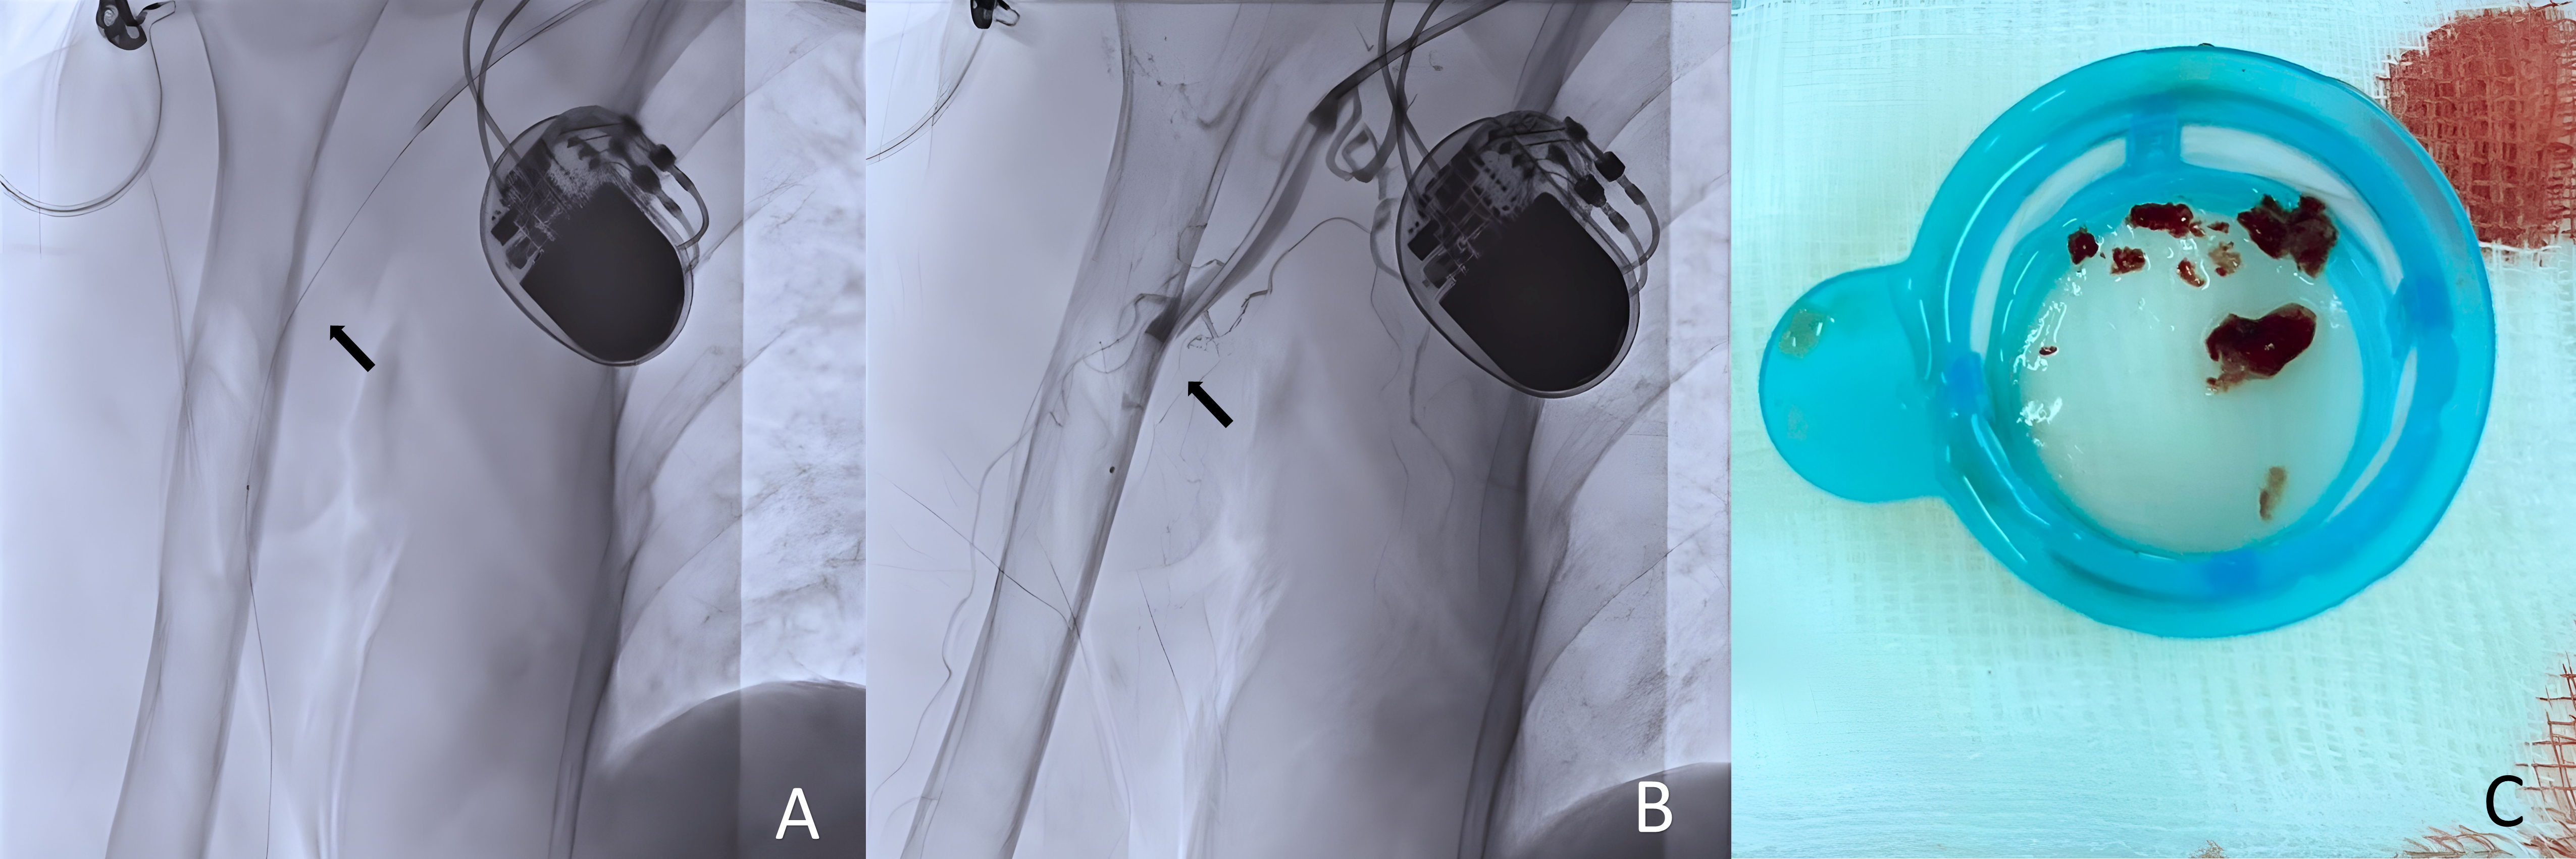

Interventions utilized a 6 Fr JR 3.5 guiding catheter via the left femoral artery, avoiding double-puncture access to minimize bleeding. Simple manual thrombus aspiration employed a 7 Fr Thrombuster II and 5 Fr Heartrail II ST01 for efficient removal. Catheter-directed thrombolysis employed alteplase (initial 4 mg bolus, followed by 1 mg/h over 24 hours) delivered directly into the thrombus via coronary thrombosuction or a guiding catheter (Figure 5-6.A), tailored for renal function preservation, with <20 mL of contrast used in one case. Serial angiography confirmed successful restoration of brachial, radial, and palmar arch flow, with TIMI-3 grade patency (Figure 5-6.B), with thrombus particles collected after thrombus retrieval (Figure 5-6.C). Only minimal transient bleeding occurred in the elderly case. Both patients were discharged on appropriate oral anticoagulation.